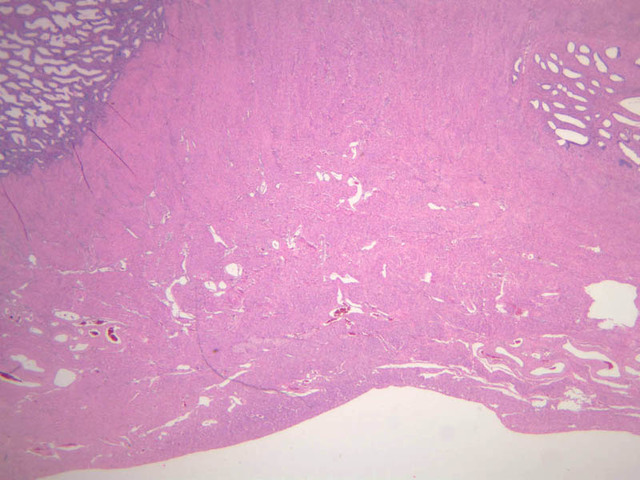

Mammary Gland

The resting or inactive mammary gland consists of predominantly dense connective tissue with small clusters of ducts and a few glandular elements (slide A-93 [2.5x-labeled, 10x, 20x, 40x] [1x, 2.5x, 10x, 20x]). It is difficult to differentiate between small ducts and alveoli as each is lined by simple low cuboidal cells. Lobes and lobules are not well defined. During puberty, predominantly under the influence of the ovarian hormone estrogen, the glandular or epithelial ducts proliferate and begin to differentiate into clusters of ductal and alveolar units termed terminal ductal lobule units (TDLUs). The non-pregnant gland will form multiple TDLUs that will not fully differentiate until pregnancy-induced growth. TDLUs are classified into Type I, Type II and Type III based on density of the ductules within each lobular unit. Type I and Type II lobules are typical of inactive glands that have not undergone a pregnancy cycle. Type III lobules are seen only in active glands or in inactive glands that have been through a pregnancy. Intralobular connective tissue is loose connective tissue that surrounds the alveoli and ducts within a lobule. The interlobular connective tissue is dense and contains considerable adipose tissue.

During pregnancy, predominantly under the influence of the ovarian hormone progesterone and the pituitary hormone prolactin, the glandular elements proliferate and differentiate to form milk-secreting units. In later stages of pregnancy, alveolar development becomes prominent and the amount of connective tissue and adipose tissue decreases. The secretory cells hypertrophy and accumulate secretory product.

The mammary gland in its active state is a compound tubuloalveolar gland (slide A-92 [10x, 20x, 40x-labeled] [2.5x, 10x, 20x, 40x]; A-94 [2.5x, 10x, 20x, 40x]). At this time, the gland is predominantly glandular tissue. Each alveolus is lined by a simple cuboidal epithelium. At the base of these cells, and within the alveolar basal lamina, are the stellate-shaped myoepithelial cells that are highly contractile and function to facilitate milk ejection.